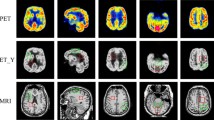

Multi-modality image fusion refers to integrating series of images acquired from different sensors and obtaining a fused image which is expected to provide more comprehensive information. It plays a pivotal role in many computer vision tasks and promotes the performance of subsequent applications. Most existing approaches attempted to design appropriate fusion rules for specific image fusion task, which have a bad generalization to different fusion tasks. Apart from that, the texture details in the fused images are common blurred due to undesirable artifacts introduced from the different modalities. In this paper, we propose a generic multimodal image fusion framework by combing the visual saliency model and flexible bilevel paradigm. Specifically, we decompose input images into an intensity layer, representing large-scale intensity variations, and a detail layer, containing small textures changes. Then we fuse the intensity layer through visual saliency map to improve the contrast of an image under consideration, and design a bilevel paradigm for fusing the detail layer to obtain fine details. Furthermore, to make the fused result visual friendly, a deep prior is built in the bilevel paradigm. Besides, an elastic target-guided hyper-parameter is introduced to dominate the proportion of the textural details from the source images, which can be further adjusted in accordance with different fusion tasks. We conducted the experiments on three available datasets to demonstrate the superiority of our framework against the state-of-the-art methods quantitatively and qualitatively in a variety of fusion tasks, including infrared and visible image, near-infrared and visible image fusion and multimodal medical image fusion.